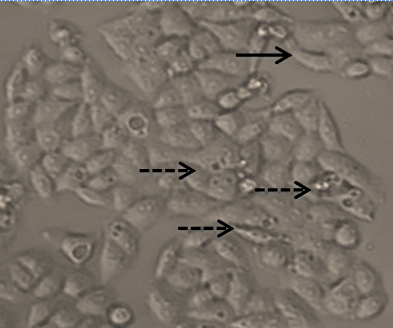

Fig. 5: Effect of Brazilein on MCF-7/DOX Cell Viability (A). Cell viability diagram was obtained from average ± standard of error (SE) with n=3. The cytotoxic effect images of untreated control MCF-7/DOX cells (B1); after 24 h Brazilein 10 µM (B2); Brazilein 25 µM (B3); Brazilein 50 µM treated MCF-7/DOX cells (B4), normal cell morphology, change in cell morphology

According to Teng et al. (2005) [22], compounds with IC50 values below 50 µM had a potent cytotoxicity against cancer cells, meaning brazilein had cytotoxic effect in MCF-7/DOX cells and brazilein performed as a potent chemopreventive agent. This effect was supported by the morphological changing such as cell nuclei appear shrunken, irregular morphology and some cells undergo membrane blebbing.